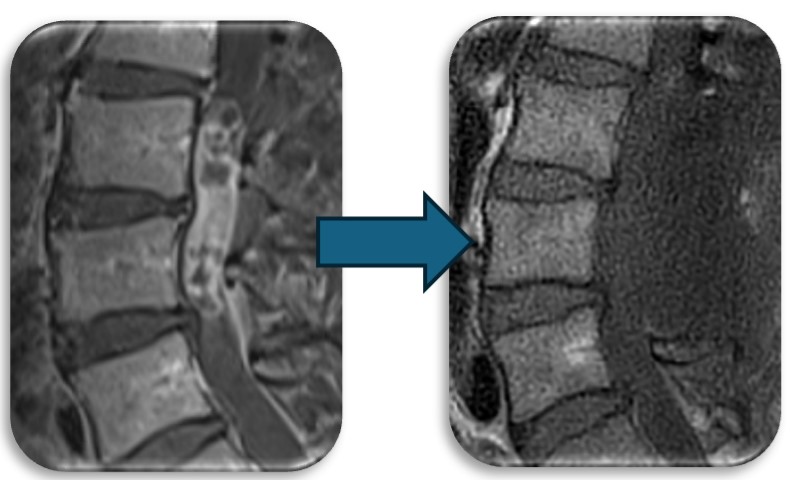

硬膜動静脈瘻の症例です。脊髄血管奇形の中では最も多い疾患です。脊髄の静脈に動脈血流が直接流入する事により脊髄浮腫をきたし(赤矢印)、様々な神経症状が出ます。最近では血管内から治療することもありますが根治率は20%程度と非常に低く、基本的には高い確率で根治できる外科的治療を施します。当院では基本的には外科的治療を選択しますが、高齢者や外科的治療が困難な症例では血管内治療を検討することもあります。手術では動脈から静脈に直接流入する部位(緑矢印)を焼灼離断します。術直後に脊髄浮腫は改善し、造影CT検査で描出の認めた異常血管影(青矢印)は術後に消失しました。

(代表例②)

頚部にできた血管奇形の症例です。当初脊髄腫瘍という話で紹介された症例でしたが、巨大な血管奇形でした(赤矢印)。椎骨動脈と脊柱管内の静脈に異常なシャントが原因で巨大な静脈瘤を呈し、それが脊髄を圧迫し神経症状を来していました。この症例はもともと神経繊維腫症1型という遺伝子疾患の既往があったのですが、まれに頚椎や頚椎周囲の血管に奇形を呈することがあります。このような症例は外科的治療は危険性が非常に高く、血管内治療で治療しました。なお、この症例は環軸椎亜脱臼も呈しており今後時期を診て脊椎手術も行う予定です。